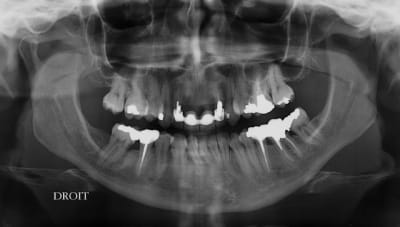

étonnant en effet... et encore plus étonnant, ce qui n'arrive jamais le radiologue (qui est parfaitement compétent normalement) a inversé la droite et la gauche.

Oui et un peu particulier au niveau de 12/22, le bridge a été fait suite à un accident sur 11/21, mais soit l'accident était grave, soit le confrère Marocain, un peu pressé.

Ceci a d’ailleurs guidé mes choix, qui ne sont pas forcement évidents, mais Primum non nocere... enfin pas plus que ce qui est déjà fait.

le scan n'est pas terrible, mais suffisant pour voir que 22 une fois extraite, ne va pas etre simple à implanter, par contre 11/21 avec un peu d'expansion...